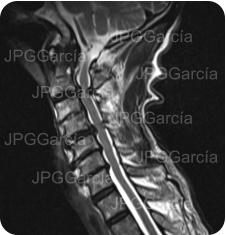

Tratamiento de hernia de disco cervical alta con compromiso medular

Estudio de control postquirúrgico inmediato